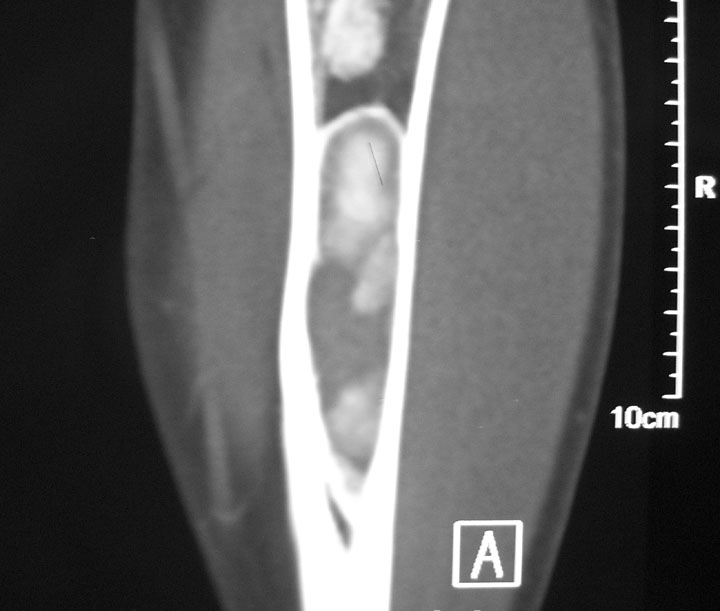

标题: CT19885:左胫骨上端肿瘤。 [打印本页]

标题: CT19885:左胫骨上端肿瘤。

男,20岁,医学院学生,11年前感左胫骨上端劳累后酸痛,曾由父母带到国内好几家有名望的医院诊治,但众说不一,所以基本上没有治疗。今年三月又开始出现症状,又到多家省级医院求治,但专家们的意见还是不能统一。各生化检查正常。mri考虑到胫骨上端良性血管瘤可能性大。ct考虑纤维瘤可能性大。请各位发表高见。

考虑左胫骨良性骨肿瘤或骨肿瘤样病变(多发性内生骨瘤?骨纤维结构不良?)。

考虑胫骨多发性内生骨瘤可能。应该传骨窗。

考虑左胫骨良性骨肿瘤或骨肿瘤样病变(多发性内生骨瘤?骨纤维结构不良?)。骨梗死,纤维瘤。